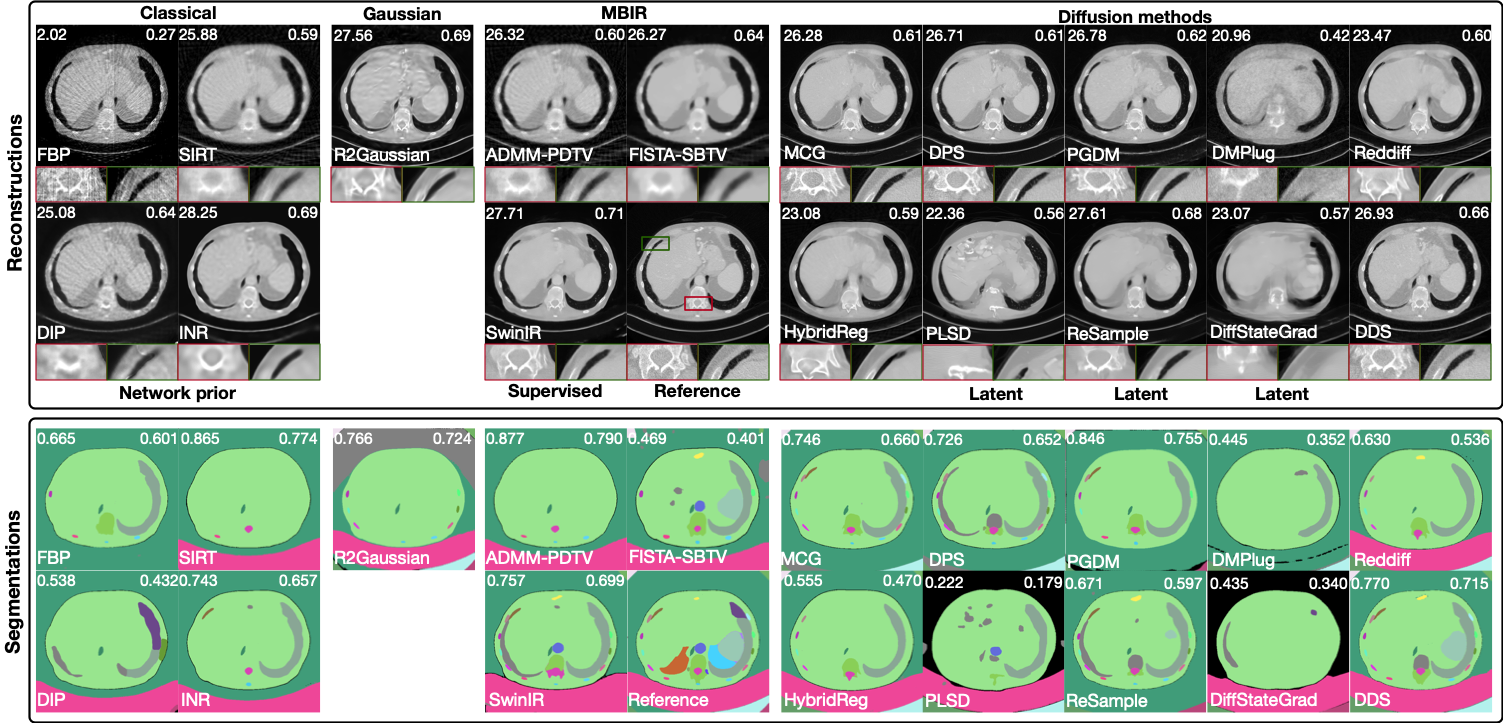

Refer to caption

Figure 2: Reconstruction results of diffusion-based and other established methods. Top: medical dataset (config iv, 80 angles with noise & ring artifacts); middle: industrial dataset (config ii, 20 angles with mild noise); bottom: real-world synchrotron dataset (60 angles). Red and green boxes show zoom-in regions. PSNR and SSIM appear in the top-left and top-right of each image. A dash (–) indicates that the method exceeded the 40 GB GPU memory limit for single-slice reconstruction and is therefore not executed. Images are consistently linear rescaled across methods to improve contrast.

Reconstruction Performance. As shown in Table 2, diffusion-based methods generally outperform classical and MBIR approaches in terms of PSNR and SSIM, but often fall short of fully supervised SwinIR. The INR-based approach achieves comparable metrics to diffusion methods, particularly in the noiseless scenario (config i) and on the real-world dataset. Visual examples in Figure 2 reveal that diffusion models tend to recover fine structural details that appear realistic but may diverge from the true reference, thereby reducing metric alignment. In contrast, INR and SwinIR produce smoother reconstructions, resulting in higher quantitative scores despite a loss of high-frequency details.

Among diffusion models, no single method or subclass (e.g., pixel vs. latent diffusion) consistently outperforms the others across all datasets and configurations, either visually or quantitatively. Performance on the real-world dataset is generally worse than on simulated data, likely due to factors such as limited training data quality and distribution shift. Perceptual metric LPIPS and full visual comparisons are discussed in Appendix A.14.